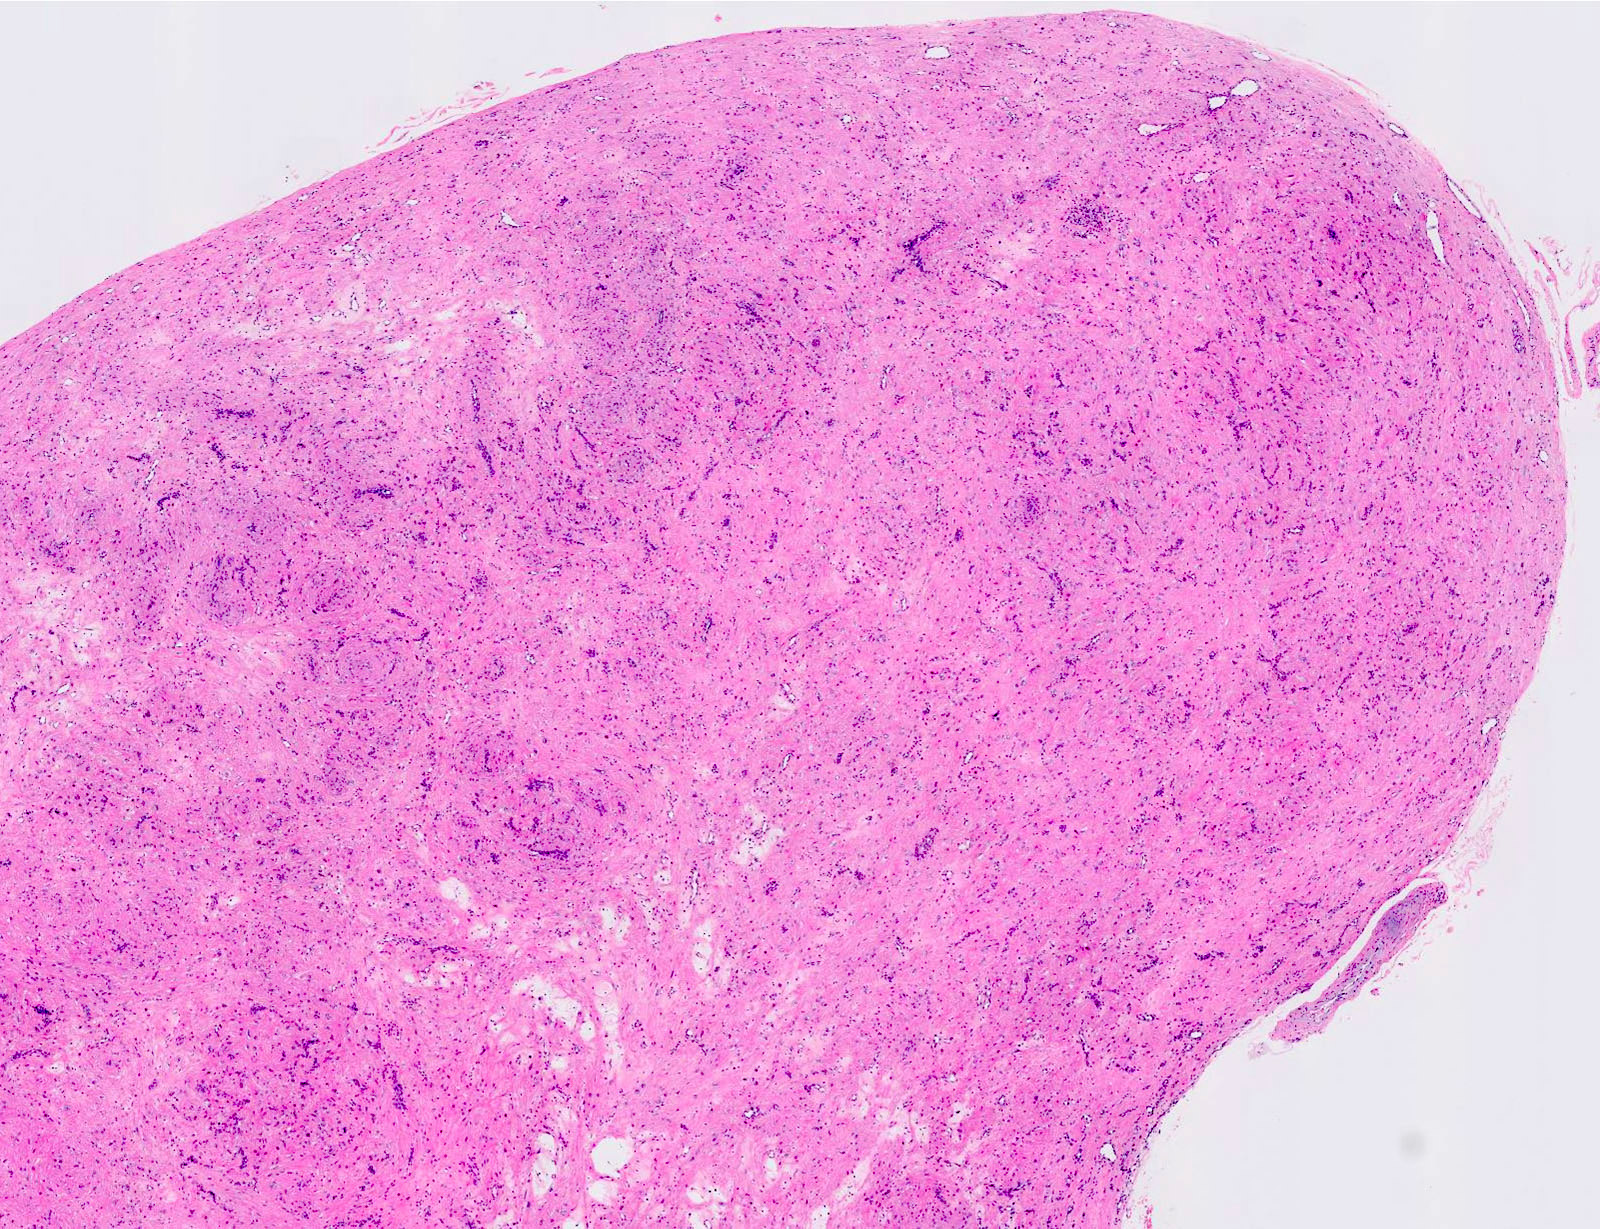

Gross description

- Sharply demarcated, spherical, gray-white or brown tumor

- Usually measuring less than 2 cm in diameter in approximately 80% of cases

Microscopic (histologic) description

- Encapsulated proliferation of eosinophilic smooth muscle cells with minimal nuclear pleomorphism

Microscopic (histologic) images

Contributed by Ohoud Aljarbou, M.D., Jijgee Munkhdelger, M.D., Ph.D. and Andrey Bychkov, M.D., Ph.D.